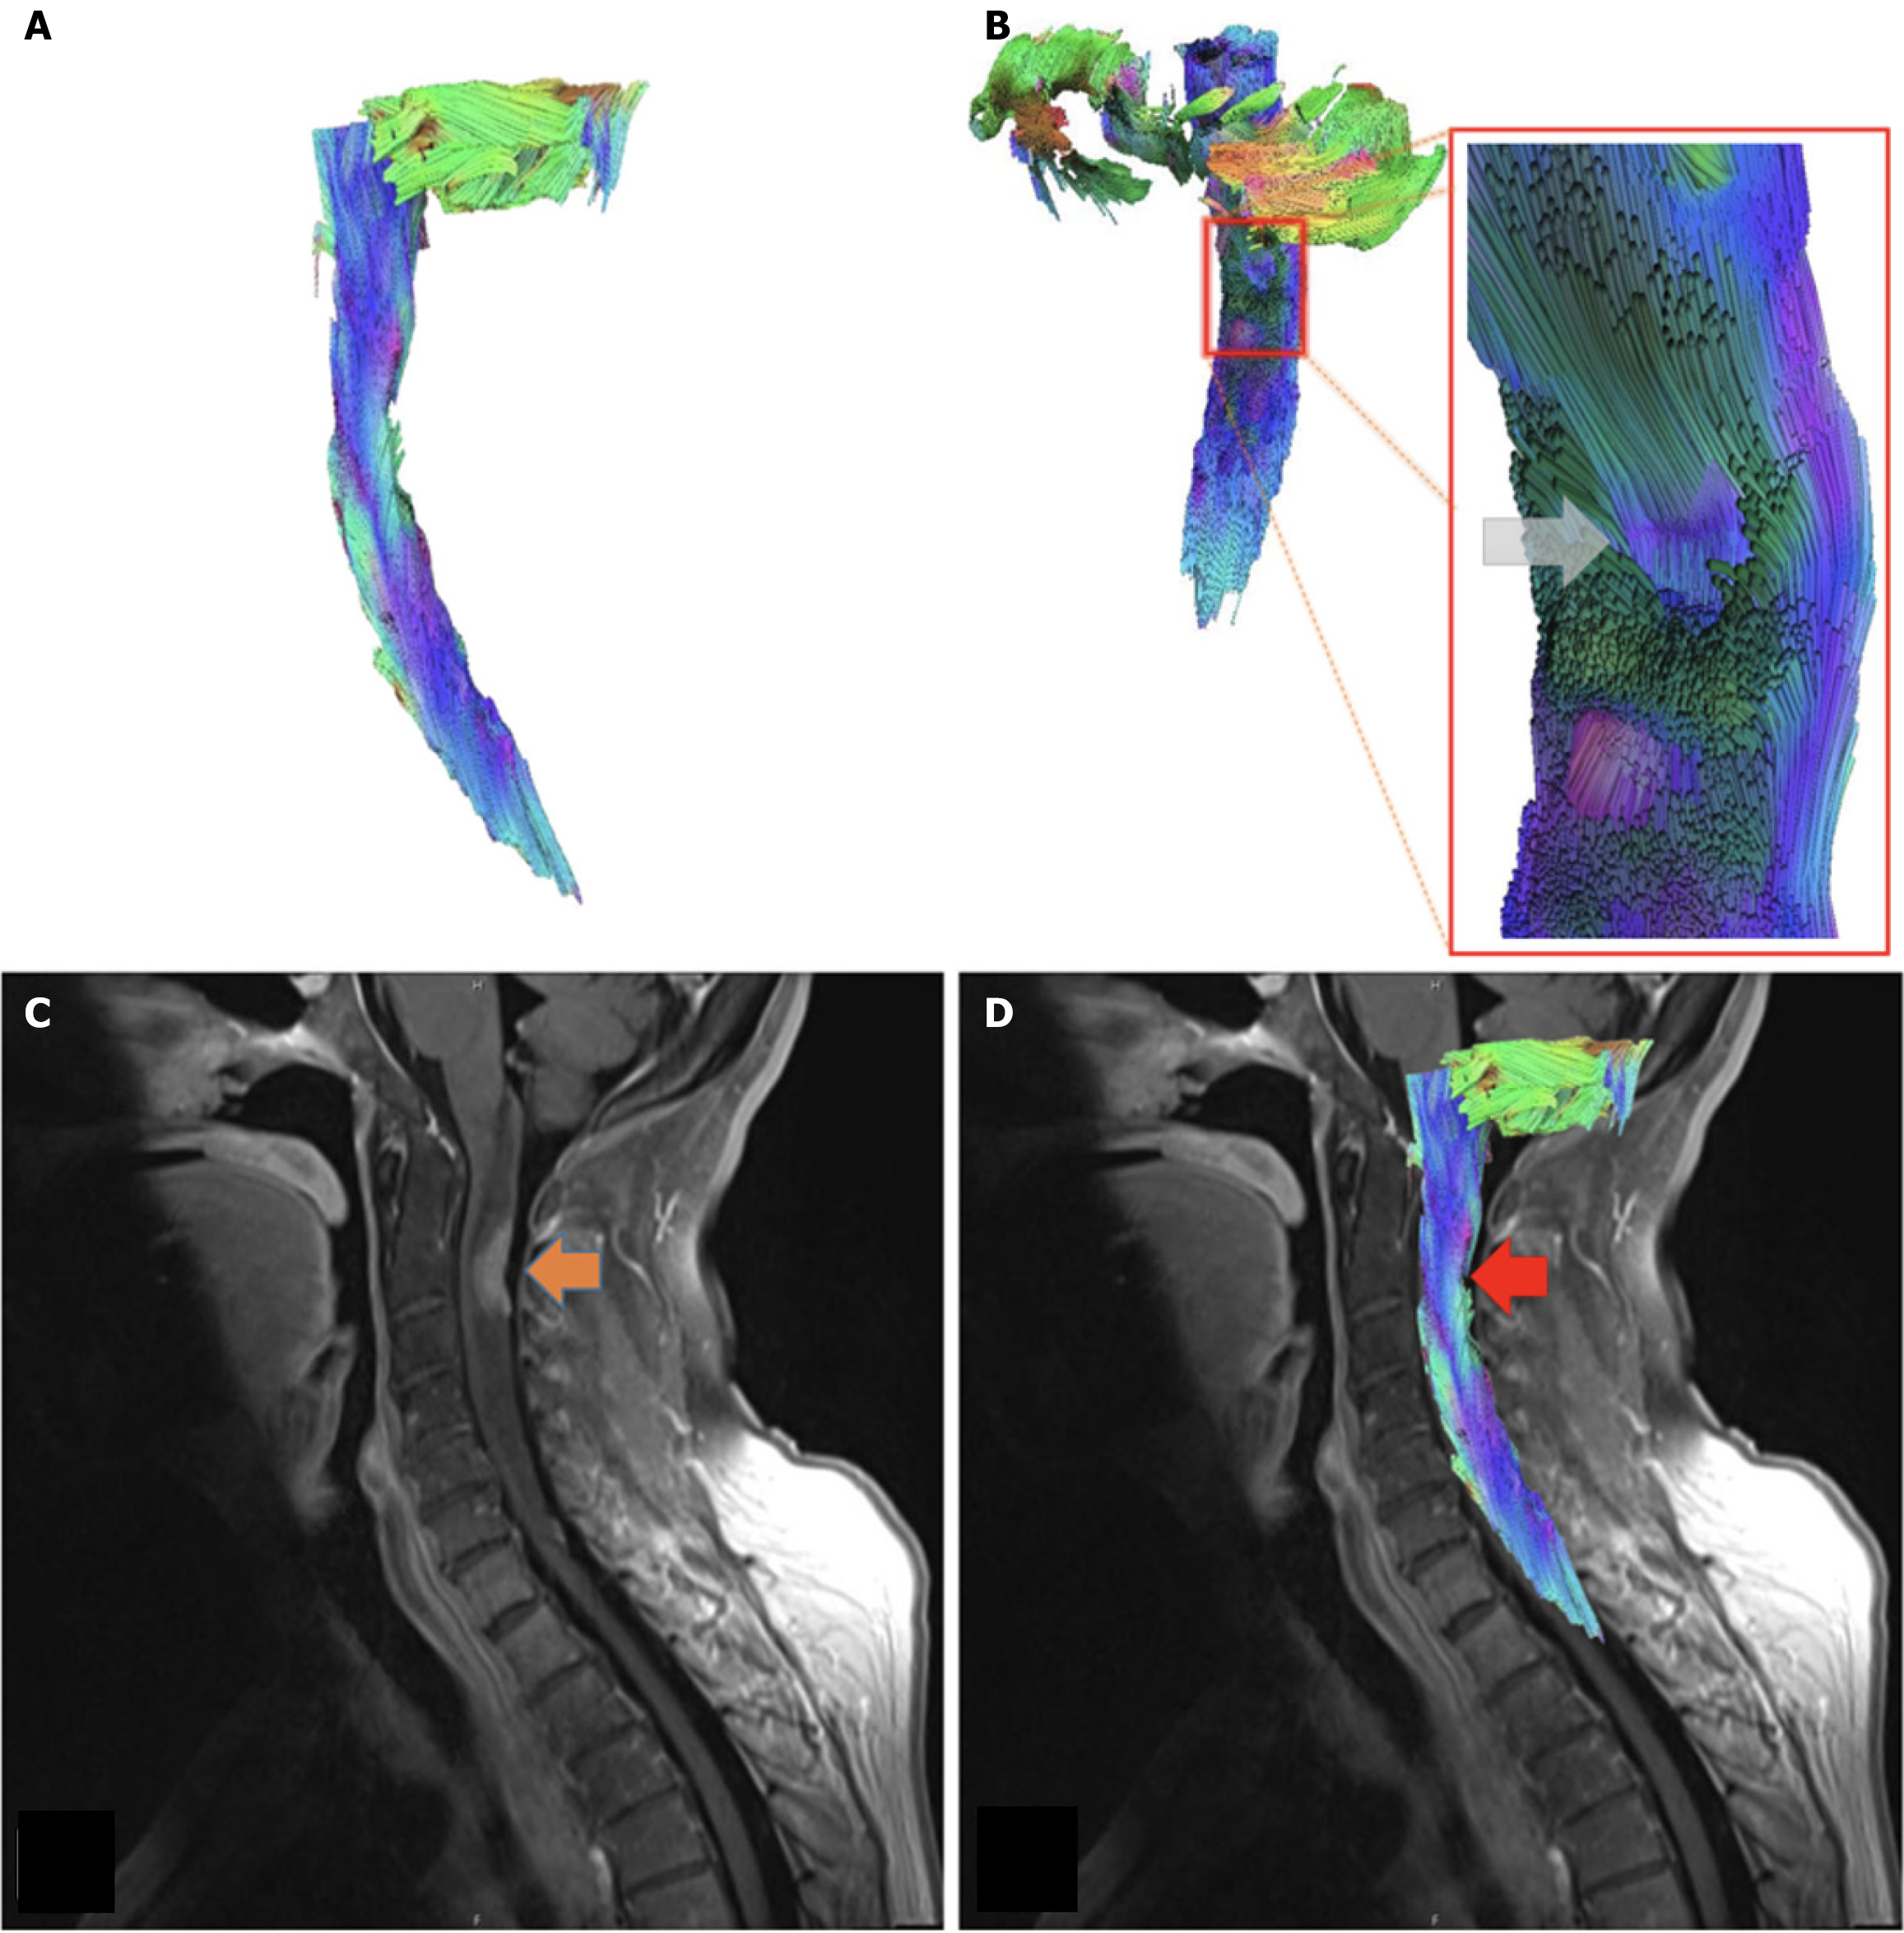

Figure 3 Metastasis case.

A: Sagittal view of tractography model. Case of 62-year-old female with primary breast cancer, displaying metastases to the lungs, spine, and brain; B: Posterior oblique view of the cervical spinal cord tractography model, with associated close up at the level of C2-C3. Note displaced fibers at the site of lesion (gray arrow); C: T1 FR STIR sagittal view of the cervical spinal cord. Metastatic lesion located at C2-C3 (orange arrow); D: Tractography model of metastasis case superimposed over T1 FR STIR sagittal view of the cervical spinal cord. The metastatic lesion can be seen at the level C2-C3 (red arrow).